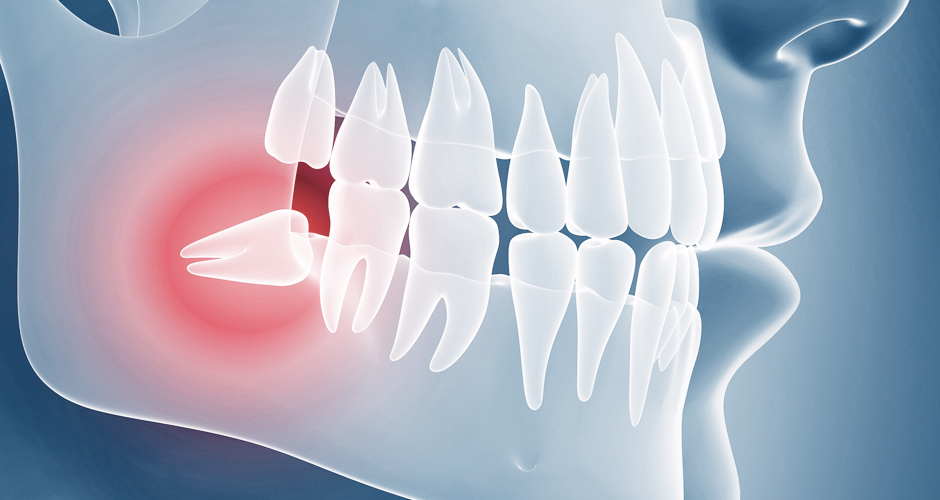

사랑니와 어금니 사이에 음식물이 끼게 되어 충치 및 치주염 발생의 위험율이 높아집니다.

임신을 앞둔 여성의 경우 사랑니에 염증이 생기면 치료가 곤란하여 매우 심한 고통을 받을 수 있습니다.

잇몸에 염증이 생겨 임파선이 붓고, 심한 경우 입이 잘 벌어지지 않을 수 있습니다.

앞 치아의 뿌리 부분을 밀어 뿌리가 흡수되는 경우가 생길 수 있습니다.